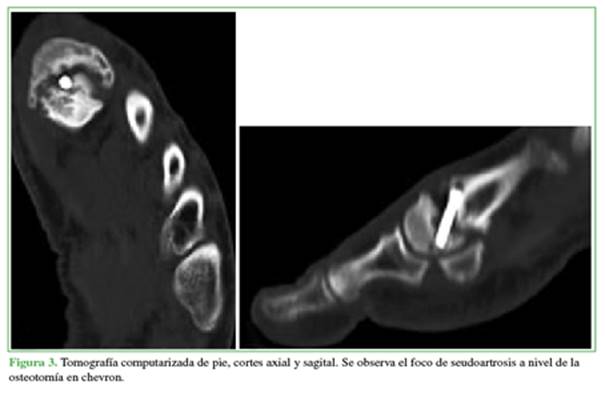

De esta manera, la serie quedó conformada por cinco pacientes (4 del sexo femenino y 1 del sexo masculino) que contaban con estudios por imágenes compatibles con seudoartrosis a los seis meses de la operación (Figuras 2 y 3). Se empleó el puntaje de la escala de la AOFAS (American Orthopaedic Foot and Ankle Society) antes de ambos procedimientos (cirugía inicial del hallux valgus y cirugía de la seudoartrosis) y después.